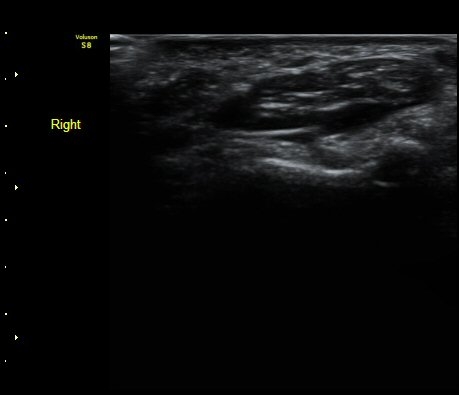

ÃÊÀ½ÆÄ °Ë»ç

¼ÒÁö±¸ ³»Ãø¿¡ ȾÀ¸·Î ŽÃËÀÚ¸¦ ´ë¾î °¥°í¸®»À °¥°í¸® ³»Ãø¸é ÇÇÁú°ñÀ» °üÂûÇÏ´Ï(¾Æ·¡ ±×¸²)

°¥°í¸® ÇÇÁú°ñ ¿¬¼Ó¼º ¼Ò½Ç(loss of cortical continuity of hook of hamate)ÀÌ °üÂûµÈ´Ù(±×¸² 1, 2).

ÇÇÁú°ñ ¿¬¼Ó¼º ¼Ò½ÇÀº °ÇÃø°ú ºñ±³ÇØ¸é ´õ¿í ¶Ñ·ÈÇÏ´Ù(±×¸² 3, 4).